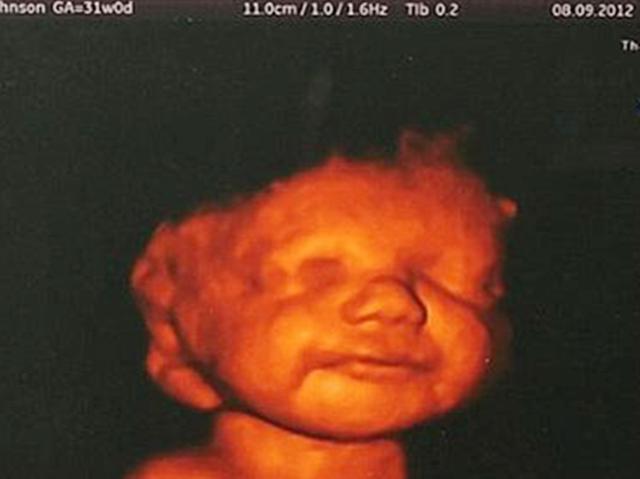

实际上 , 宝宝在子宫内时 , 就已经学会笑了 。

根据一位英国医学专家公布的一张胎儿微笑的照片看 , 胎儿在第十七周时就有感知心情的能力了 。

孕妇一家听到医生这么说也同意放弃 , 可随后做了三维彩超后 , 发现胎儿的脸上竟然洋溢着幸福的微笑 。